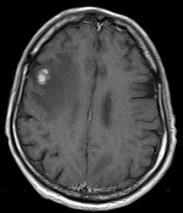

问题 关于颅内转移瘤(如图所示),以下哪项正确()

选项 A.常为单发 B.淋巴转移为常见转移途径 C.多见颞叶 D.最常见的原发病变是消化道肿瘤 E.多见于大脑中动脉分布区

答案 E